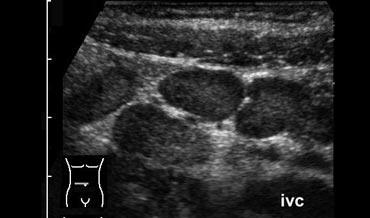

Vỡ phình động mạch

Hầu hết các phình động mạch chủ bụng vỡ vào khoang sau phúc mạc bên trái (4).

Về mặt lâm sàng, điều này có thể bắt chước viêm túi thừa đại tràng sigma hoặc cơn đau quặn thận do khối máu tụ chèn ép vào các cấu trúc lân cận.

Tuy nhiên, hầu hết bệnh nhân sẽ biểu hiện với tam chứng kinh điển gồm tụt huyết áp, khối đập theo nhịp mạch và

đau lưng.

Rò rỉ liên tục sẽ dẫn đến vỡ vào khoang phúc mạc và cuối cùng là tử vong.

Siêu âm là phương tiện nhanh chóng và tiện lợi, nhưng độ nhạy và độ đặc hiệu trong chẩn đoán vỡ phình mạch thấp hơn nhiều so với CT.

Việc không có bằng chứng vỡ phình mạch trên siêu âm không loại trừ được bệnh lý này nếu nghi ngờ lâm sàng cao.